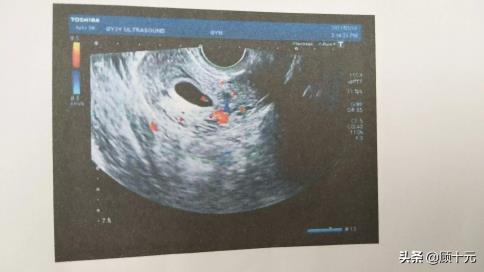

孕38周下列是我全部孕期所做的一切检验和所耗费的费用!2021年2月20日:试管移植后第14天回院验孕抽血,确认有孕,抽血只检验了HCG,花了57.1元,挂号费30元,共计87.1元。2021年3月5日:第一次B超,是阴超。以确认有没有胎心胎芽!耗费190元,挂号费20元,共计210元。

2021年3月13日:三更忽然见红,吓得不轻,去医院抽血查孕酮和HCG,共耗费153.88元,挂号费6元,共计159.88元。2021年3月19日:第二次B超,阴超,确认胎心胎芽,耗费190元,挂号20元,共计210元。2021年4月22日:由于小腹一直隐约作痛,去医院查了B超,耗费133.5元。2021年4月29日:第十二周建档,当天耗费1298.2元,做的检验有点多,每个地区不同样,这我就不一一罗列了。2021年6月8日: 做了中唐,耗费180.8元。2021年7月13日:四维,耗费328.3元。2021年7月25日: B超 208元(懂的人都懂!)2021年8月11日: 做了耐糖量测验,花了117.7元,还做了胎儿心脏彩超,耗费183.6元,共计317.3元。另外,还做了血常规 ,耗费21.5元, 产前检验28.8元,和单光子骨密度测定47.5元,共计97.8元。2021年9月3日:(30周+4):做了二级B超 ,耗费222.5。(此中B超177.5,产前检验28.8)2021年9月17日:(32周+4):做了血常规,耗费20.1元,尿液探测25元,空腹血糖14.85元(由于此前糖耐量测验空腹血糖不合格,需复查),胎心探测2次,第一次不合格,第二次合格,分别耗费79.3元和36.1元,共计175.35元。2021年9月30日:(34周3):做了 B超,耗费189.9元, 胎监60.3元,共计250.2元。2021年10月7日:(35周3):胎监67.1元, 尿液探测25元,白带(B族链球菌核酸定量探测)120.3元,共计212.4元。2021年10月14日:(36周3):只做了胎监,60.3元。2021年10月21 日:(37周3):胎监 60.3 元,尿液探测25元,胎监不合格需重做36.1元,共计121.4元。2021年10月28日:(38周3):胎监 60.3 元,尿液探测25元,B超189.9元, 血常规20.1元,共计295.3元。2021年11月4日:(39周3):胎监 69.3元。2021年11月11日:(40周3):胎监69.3元, B超189.9元,共计259.2元。2021年11月17见红住院,18日顺产,临盆费用:4808.15(由于产后大出血 ,因此我的费用比通常顺产贵一点。)